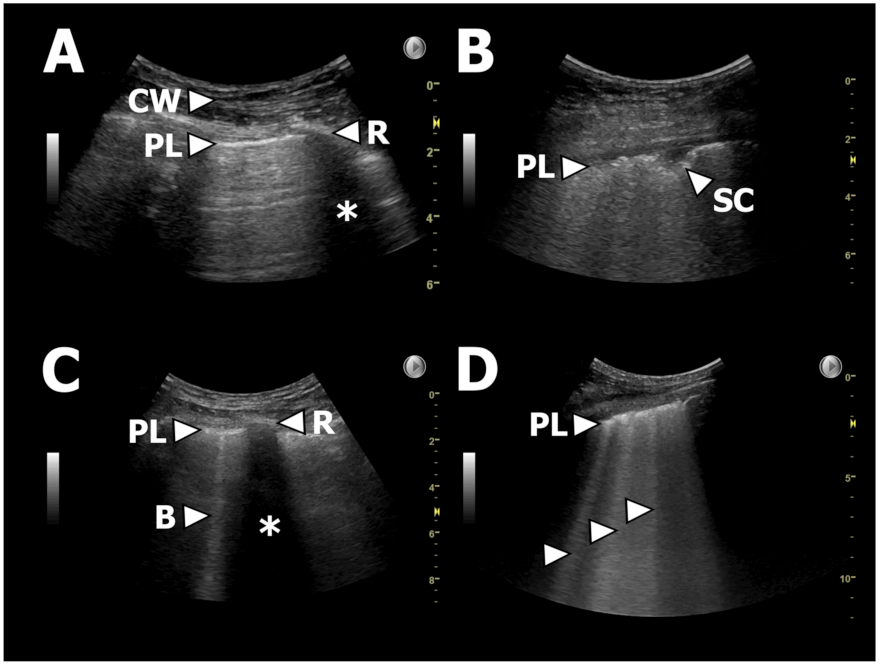

B-lines, IS, and pleural thickening are LUS findings known to be associated with presence of fibrosis identified on HRCT [21,22,23,24,25,26,27]. We hypothesized that presence of these LUS findings in new-onset CLAD could act as surrogate markers of a radiological PPFE pattern verified on HRCT in patients with RAS. In such LUS could be a supplementary diagnostic tool to phenotype RAS from BOS in whom these LUS findings are not expected [32]. We used the following definitions (Figure 2):

Figure 2.

Examples of LUS findings. (A): Normal LUS. PL = pleural line, CW = chest wall, R = rib, * = rib shadowing. (B): Thickened/fragmented pleura and a small subpleural consolidation. PL = pleural line, SC = subpleural consolidation. (C): Single B-line. PL = pleural line, R = rib, * = rib shadowing, B = B-line. (D): Multiple B-lines as part of, e.g., IS. PL = pleural line, arrows = B-lines.

Number of B-lines: B-lines were defined as vertical reverberation artefacts originating from the pleural line extending uninterrupted to the edge of the screen on the ultrasound machine without fading (previously termed “comet-tails”) [21].

Interstitial syndrome (IS): ≥3 B-lines in ≥2 anterior or lateral zones on each hemithorax [22,23].

Upper lobe IS: ≥ 3 B-lines in in both zone R/L1 and R/L7.

Pleural thickening: Pleura thickness >1 mm regardless a normal or abnormal irregular or fragmented presence of pleura [26,33].